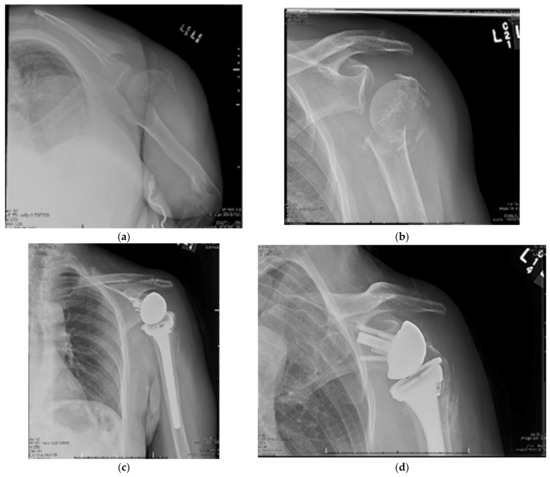

13. Reverse Total Shoulder Arthroplasty

15. Hemiarthroplasty